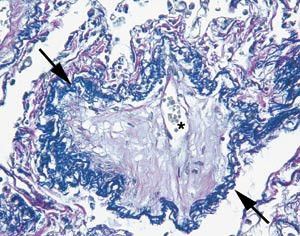

Ved autopsi var høyre ventrikkel hypertrofisk med veggtykkelse på 7 mm og høyre atrium forstørret. Det var aterosklerotiske plakk proksimalt i begge lungearterier, med mindre trombotiske påleiringer perifert uten tegn til okklusjon. Mikroskopisk undersøkelse viste tydelig veggfortykkelse av små kar, og tynnveggede vener var vanskelig å identifisere. Ved elastinfarging fant vi betydelig intimafibrose, til dels med obliterasjon, i mange små lungevener (fig 2). Pleksiforme lesjoner som er typiske ved pulmonal arteriell hypertensjon, var ikke påvisbare.

Det er enighet om at de primære patologiske forandringene foreligger på den venøse siden i lungene, selv om mediahypertrofi i arterioler også forekommer. Mikroskopisk kan forandringene på venesiden lett overses ved at fortykkede vener oppfattes som små arterier. Bruk av elastinfarging vil avklare en slik usikkerhet ved å gjøre synlig at små vener mangler den indre elastiske membran. Det histologiske bildet med obliterering og okklusjon av mindre pulmonale vener oppfattes indusert av karskade. Ulike mekanismer for traume mot karveggen er foreslått, slik som infeksjon, genetisk disposisjon, eksposisjon av toksiske substanser, trombotiske forstyrrelser og autoimmun sykdom. Vår pasient var røntgenbestrålt mer enn fem år før det aktuelle som ledd i behandlingen av underlivskreft, og det er beskrevet assosiasjoner mellom bestråling og venookklusiv sykdom (5), riktignok ved lymfom og bestråling av lungefelt. En vel så sannsynlig sammenheng kan knyttes til pasientens sklerodermi og CREST-syndrom, idet venookklusiv sykdom har vært beskrevet ved ulike autoimmune sykdommer (6, 7). En mulig mekanisme er autoimmun destruksjon av pulmonale venyler, primært eller sekundært til en viral infeksjon, med påfølgende trombose og fibrose. Da biopsifunnene ikke er entydige med hensyn til inflammatoriske forandringer, er det naturlig å tenke seg flere årsaker/agenser som alle deler de histologiske særtrekk med obliterasjon og okklusjon av de små pulmonale vener.